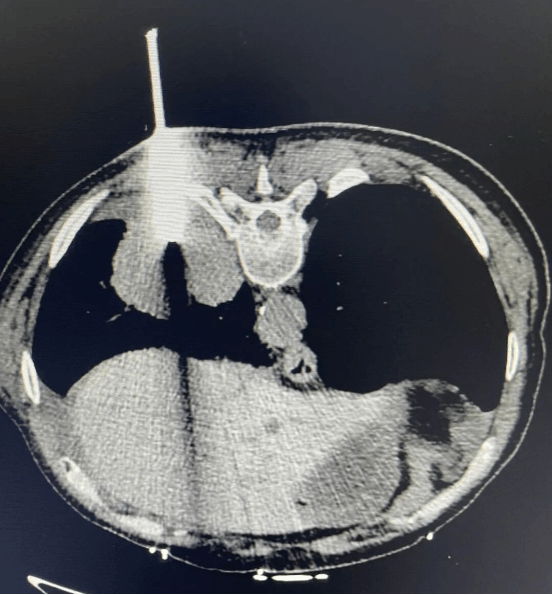

• 同样微创安全:

在CT精准引导下,冷冻活检全程创伤极小,患者恢复快,并发症发生率与传统穿刺相当,兼顾了诊断效能与医疗安全。